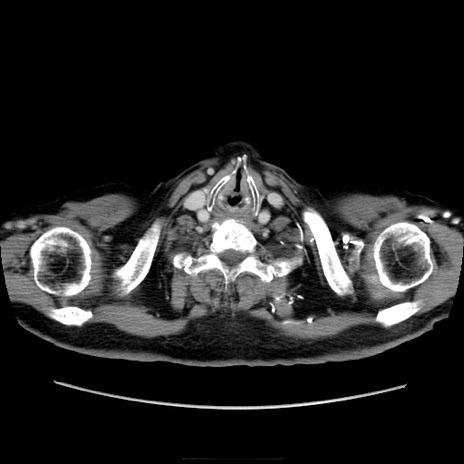

症例21(横断像)

【症例】70歳代男性

【主訴】腹痛

【現病歴】肝硬変・肝細胞癌にてかかりつけの方。約9時間前に食後より腹痛出現。症状が徐々に増悪し、嘔吐出現したため来院。

【既往歴】肝硬変、肝細胞癌(RFA、TACE後)

【身体所見】意識清明、表情苦悶様、BT 36℃、BP 129/78mmHg、P 88bpm、SpO2 97%(RA)、右上腹部から心窩部にかけて圧痛あり、反跳痛なし、筋性防御あり。

【データ】WBC 5800、CRP 0.16